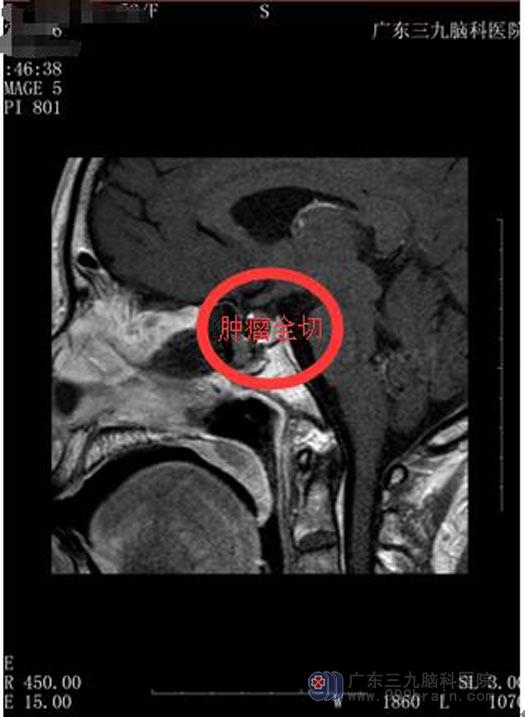

经检查,温阿姨没有明显的手术禁忌症,一家人都同意手术治疗。由鲁明主任主刀,行“经鼻蝶鞍区Rathke囊肿切除术”。术后温阿姨没有脑脊液鼻漏、离子紊乱等术后并发症,视物模糊与头痛头晕的症状得到了明显的改善。

手术后